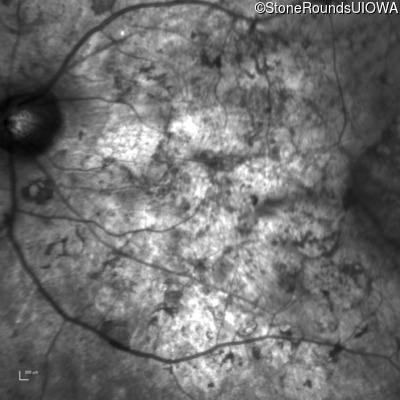

Age at visit: 33 years

OD OS